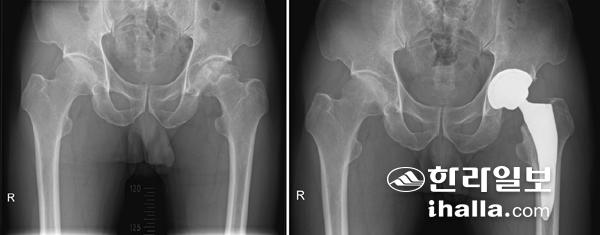

인공관절 전치환술 전 X-ray(사진 왼쪽), 인공관절 전치환술 후 X-ray

마지막 고관절 인공관절 치환술은 괴사되고 염증이 생긴 관절을 제거하고 새로운 인공관절로 치환해주는 수술이다. 가장 결과가 확실하며 가장 많이 시행되는 치료 방법이며, 나이가 많은 환자에서는 일차적으로 시행해 볼 수 있다. 과거에는 인공관절로 금속이나 플라스틱을 많이 사용했으나 최근에는 비교적 내구성이 좋은 세라믹 인공관절을 많이 쓰고 있다.